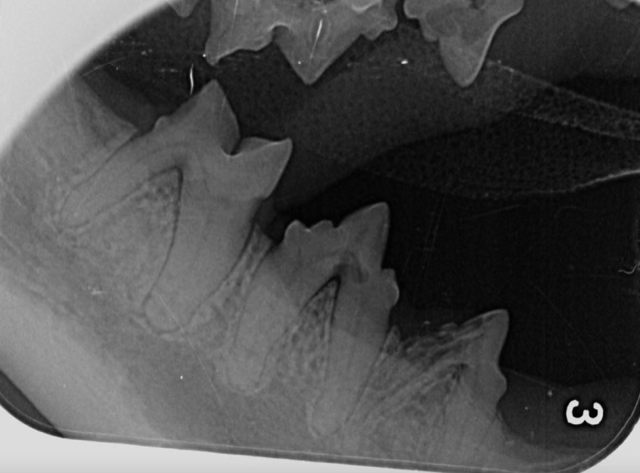

Images

Vous pouvez télécharger les images ci-dessous en cliquant dessus.